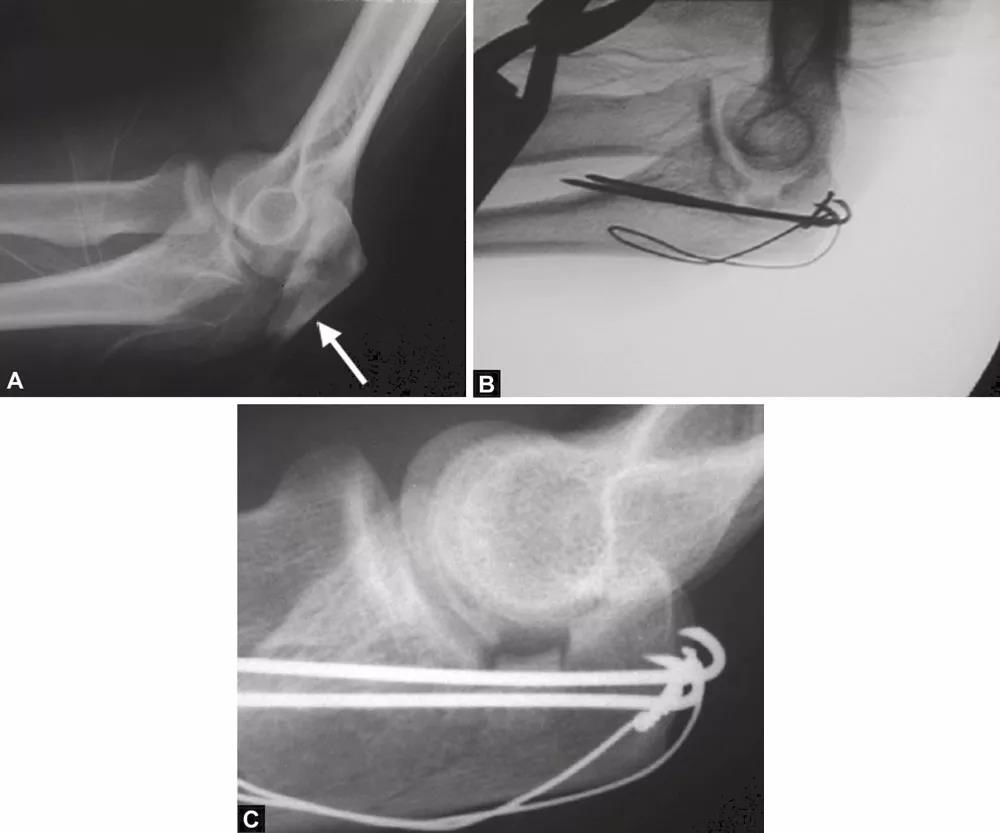

图2A~C关节面部分压缩非常不易觉察。有经验的医生会注意到鹰嘴曲线的变窄从而推断出压缩部分的存在。术中斜位X线片检查压缩骨折仍隐匿,仅在术后的X射线中越来越明显